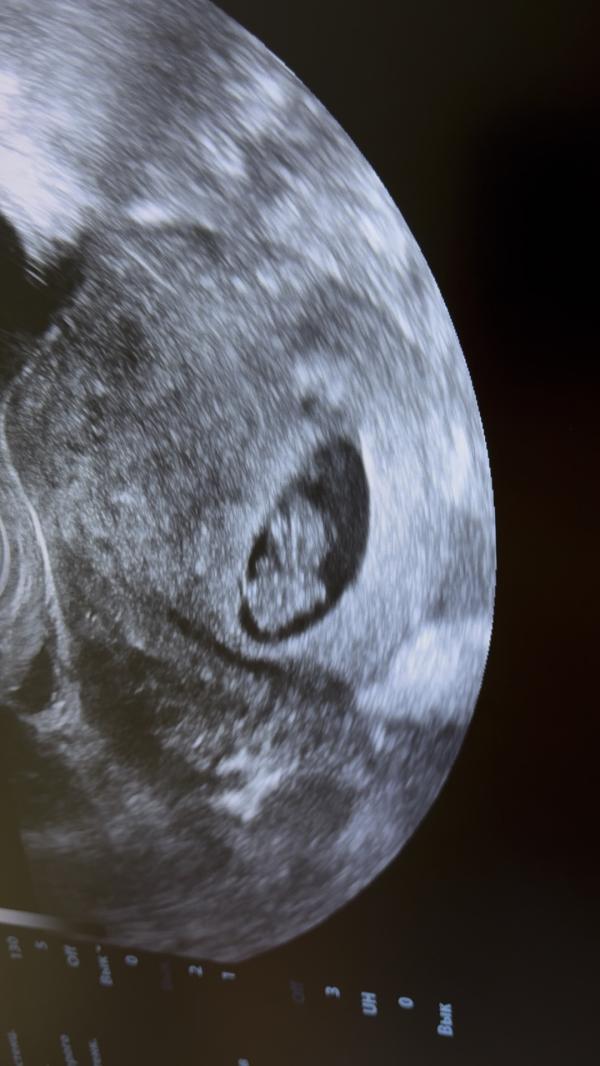

Мне надо восстановить хронологию событий, раз я не стала вести свою страничку с самого начала. УЗИ проходила каждые 2 недели. История развития маленького человека🥰 Последнее фото со скрининга на флотской, лялька с характером, совсем не давалась смотреть и фоткаться😁